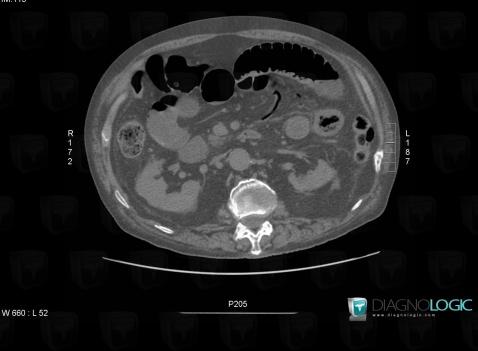

Aéromésentérie, Veine porte et ses branches, Scanner

Voici les informations spécifiques à l'image clé ci dessus:

- Diagnostic Aéromésentérie, Localisation(s) Veine porte et ses branches, comportant les gammes